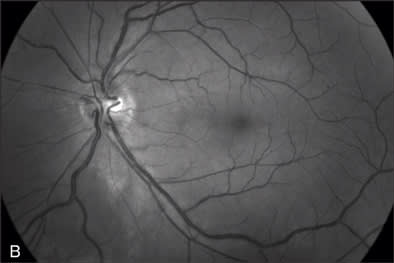

At the 5-month follow-up visit in February 2009, corrected visual acuity remained 20/20 in the left eye, with normal ocular pressure in both eyes. There were no rubeosis irides in either eye. Fundus examination appeared normal in the right eye with improvement in the appearance of the retinal vasculature in the left (Figure 2A). Fluorescein angiography of the left eye (Figure 2B to 2E) showed resolution of the CRVO characteristics (dilated, tortuous retinal veins, intraretinal hemorrhages, peripheral retinal non-perfusion areas) with no microvascular leakage at the macula. Spectral OCT confirmed no cystoid macular edema (Figure 2E).

Figure 1F demonstrates the changes of oximetry between the 2 visits. The arterial oximetry changed from blue to red (red arrow), the venous oximetry changed from green to blue (yellow arrow). The non-perfusion area in the Figure 1F (appeared in blue) disappeared as shown in the follow-up visit report (Figure 2F), this was well correlated with the changes in the FA images in Figures 1D and 2D. The change to the nerve fiber layer infarction area was also observed on the oximetry, where it primarily appeared in white (Figure 1F, black arrow) then it disappeared in the follow-up visit report (Figure 2F), this change was also well correlated with the change between the red-free images (Figure 1B, arrow outlined, and Figure 2B).

The segmental blood-flow reports (Figures 1G and 2G) were also compared and described in the details of changes. In the area in the Figure 1G (white arrow outlined) that appeared to be poorly perfused, blood-flow velocities were depressed compared to results of the same area in the follow-up visit report (Figure 2G). The segmental blood-flow value under the nerve fiber layer infarction area (Figure 1G, black arrow) had no significant change between the 2 visits. The average blood-flow values of the entire retina at the follow-up visit were 3.03 and 2.08 mm/sec for artery and vein respectively, compared with the values at the first visit of 1.11 and 1.00 mm/sec for arteries and veins respectively.